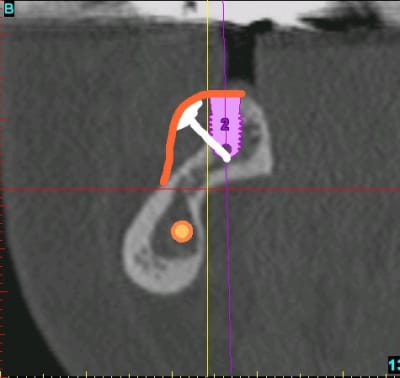

Je renouvelle ma suggestion/ question : pourquoi pas 2 vis à émergence haute, inclinée d'env 30° par rapport à l'implant, et une plus basse entre les 2 précédents orthogonale à la surface osseuse ?

C'est un peu ce à quoi je pense.

J'ai tenté de faire à la volée un crobard sur paint (c'est pas à l'échelle, j'ai fait ça entre 2...)

Si la vis est bien inclinée, on peut imaginer qu'elle ne soit pas agressive pour la muqueuse et que l'operculisation ne survienne pas. Et puis avec du matériau en excès et une membrane, une gestion des tensions avec des points adhoc, on fait tout pour que ça fonctionne, non ?

le principe c'est de se matérialiser mentalement la future crête et de disposer les vis de façon à ce qu'elles soient perpendiculaires à la future corticale et non pas perpendiculaires à la corticale déjà existante. C'est ce que l'on voit sur la coupe de clio et sur le schéma de mario.